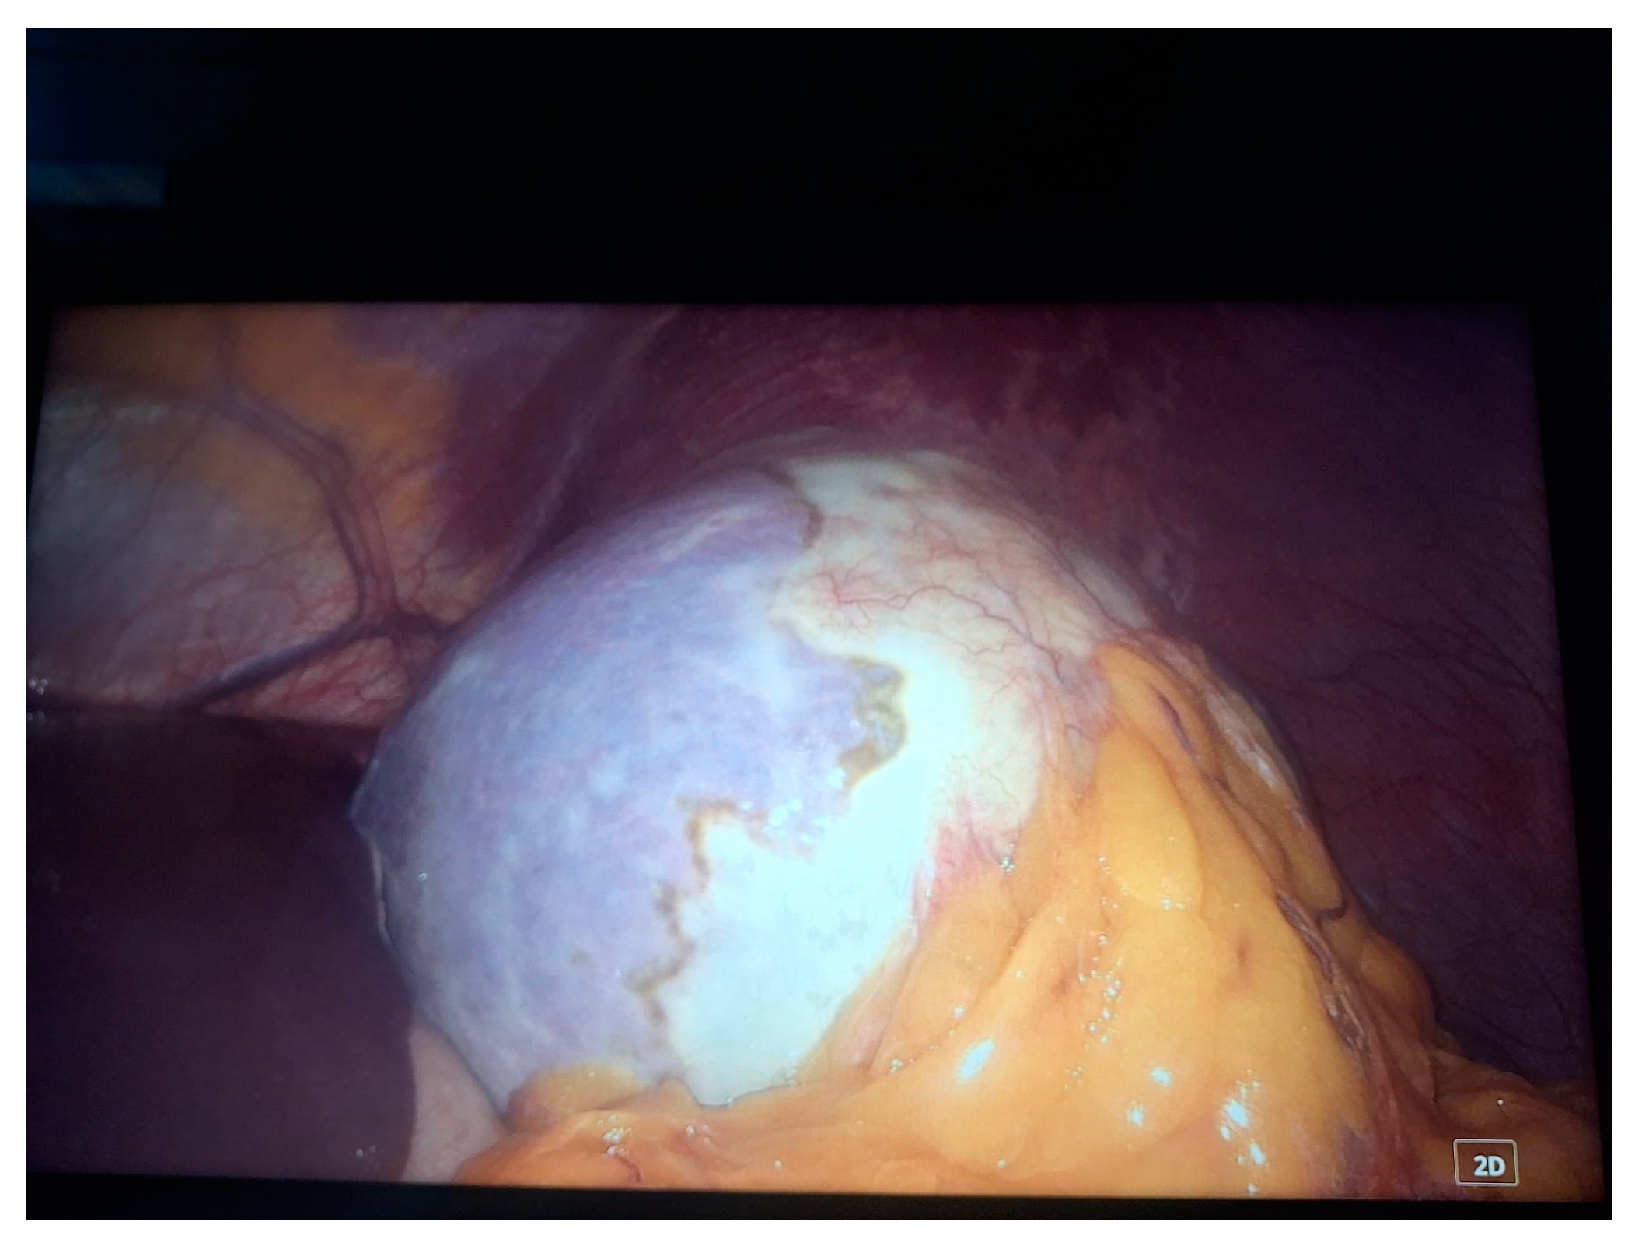

- Grade I splenomegaly with simple voluminous splenic cyst, 10 cm in diameter.